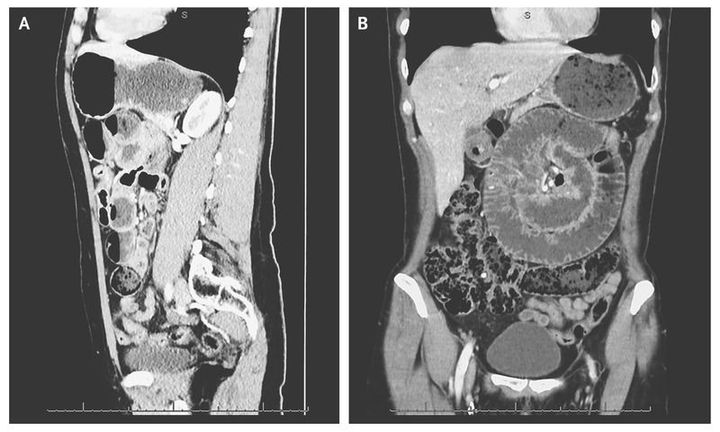

A 57-year-old woman was admitted to the emergency department with sudden-onset upper abdominal pain and vomiting. The patient's medical history was notable for type 1 diabetes and laparoscopic tubal sterilization. Computed tomography (CT) revealed small-bowel volvulus with dilated small bowel rotated around its blood supply (Panels A and B). There were no signs of free air or fluid and no indication of bowel ischemia on the CT scan. Explorative laparotomy revealed signs of strangulation of the small bowel 1 m from the ligament of Treitz. The bowel was viable, and no resection was performed. The patient was discharged in good condition 3 days later.